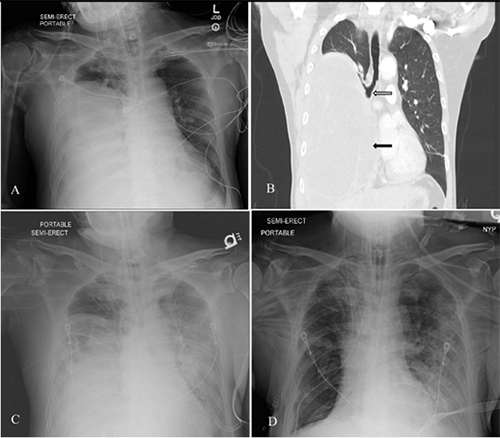

Chest CT showed a large complex mixed density cyst in the right lower thorax concerning for hydatid cyst measuring 17.1 × 15.9 × 20 cm with a compressive effect on the right mainstem bronchus and leftward mediastinal shift (Figure 1B). Bedside thoracic ultrasound was equivocal for daughter cysts. CT scan of the head, abdomen, and pelvis was negative for disseminated disease. Admission labs were significant for leukocytosis with no eosinophilia. Blood cultures on admission were negative and respiratory cultures were positive for mixed respiratory flora. Echinococcal antibodies were sent on admission to the CDC Prevention lab and were reported as negative two weeks later. No malignant cells were seen on fluid cytology. Subsequent chest x-rays showed new airspace opacities throughout the left lung concerning for pneumonia. The presumed diagnosis was a pulmonary hydatid cyst with secondary respiratory failure and shock of uncertain etiology, potentially from ruptured cysts from chest drainage and anaphylaxis. After consultation with infectious disease specialists, Albendazole was started, given presumed rupture of the cyst with worsening respiratory status and circulatory shock. IV fluids, vasopressors, and broad-spectrum antibiotics were initiated due to evidence of sepsis and left lung pneumonia on interval chest x-rays. Standing doses of steroids and antihistamines were added, given the reported incidence of anaphylaxis with a ruptured hydatid cyst.

After a multidisciplinary discussion, the patient underwent a bedside percutaneous aspiration-injection-reaspiration procedure under close monitoring, given the patient's hemodynamic instability and anticipated intolerance to operative intervention. The patient oxygen saturation was in the mid-80s despite APRV ventilatory mode under ARDS protocol with FiO2 of 100% and paralysis. Under ultrasound guidance in a sterile fashion, we performed a bedside percutaneous placement of a 24Fr chest tube followed by aspiration of the cyst contents. We initially aspirated 400 ccs of dark thick malodorous gelatinous material. We upsized the chest tube to 28Fr with Seldinger technique, allowing another 800 ccs of the same material (Figure 2A). We followed that by injecting 500 ccs of 15% hypertonic saline into the cyst. We clamped the tube for 15 minutes, followed by reaspiration drainage. Gram-positive cocci were seen, later identified as MRSA. Fluid cultures were negative for fungi, acid-fast bacilli, and ova or parasites. Postprocedural plain films demonstrated improvement in aeration in the right hemithorax (Figure 1C).

Figure 1. CT Scans. Published With Permission

A and B) CXR and CT scan of chest consistent with massive right cystic mass (black arrow) in right hemithorax with bronchial compressive effect (white arrow); C) status post-PAIR with better aeration in right and new airspace opacities throughout left lung; and D) status post-en bloc right lower lobectomy.

On postprocedural day 2, the patient's oxygenation improved, decreasing the FiO2 requirement to 60%. The patient was taken to the operative room for definitive source control. He underwent right posterolateral thoracotomy, en bloc right lower lobectomy, and full decortication. We noted that the entire right lower lobe was completely necrotic and full of cystic and gelatinous material upon entering the chest cavity. The patient had a significant air leak from the open bronchi from the bronchopleural fistulas that had developed due to necrosis. We proceeded with decortication of the right lower lobe and mobilization, followed by en bloc resection (Figure 2B). He was then transported to the ICU in guarded but stable condition (Figure 1D).